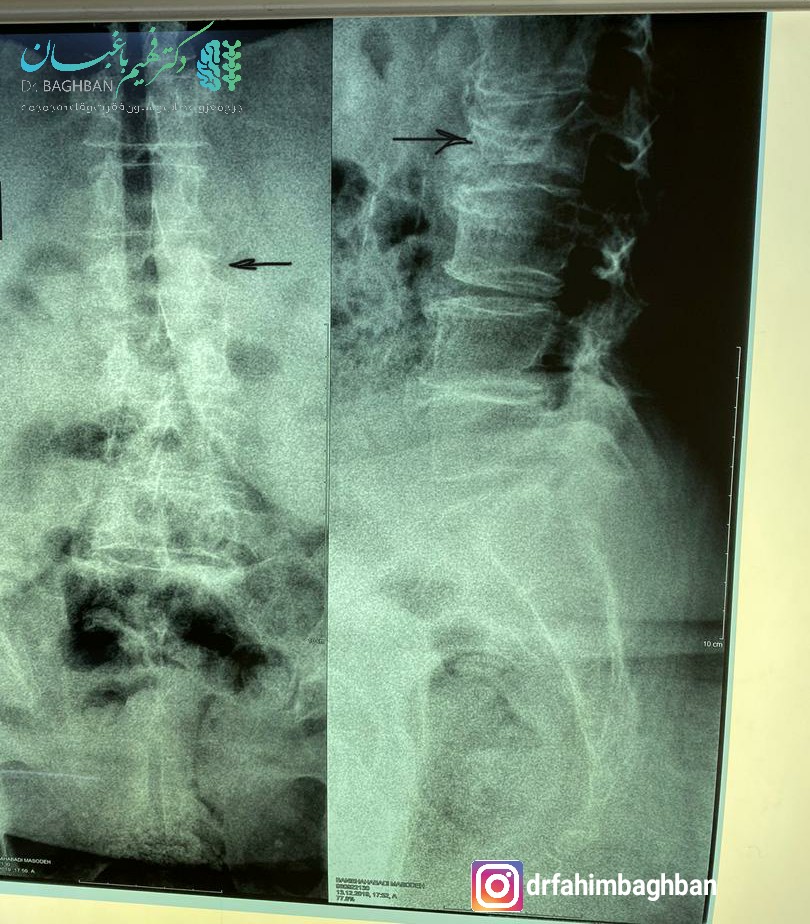

بیمار خانم ۷۴ ساله با درد شدید و ناگهانی کمر بدون سابقه ضربه مراجعه کرده بودند. تحت عمل جراحی تزریق سیمان (کایفوپلاستی) قرار گرفتند. همانطور که در تصویر آخر مشاهده می کنید مهره شکسته کاملا به ارتفاع نرمال برگشته است :

قبل از انجام جراحی

قبل از عمل

تزریق سیمان جهت رفع شکستگی مهره کمر